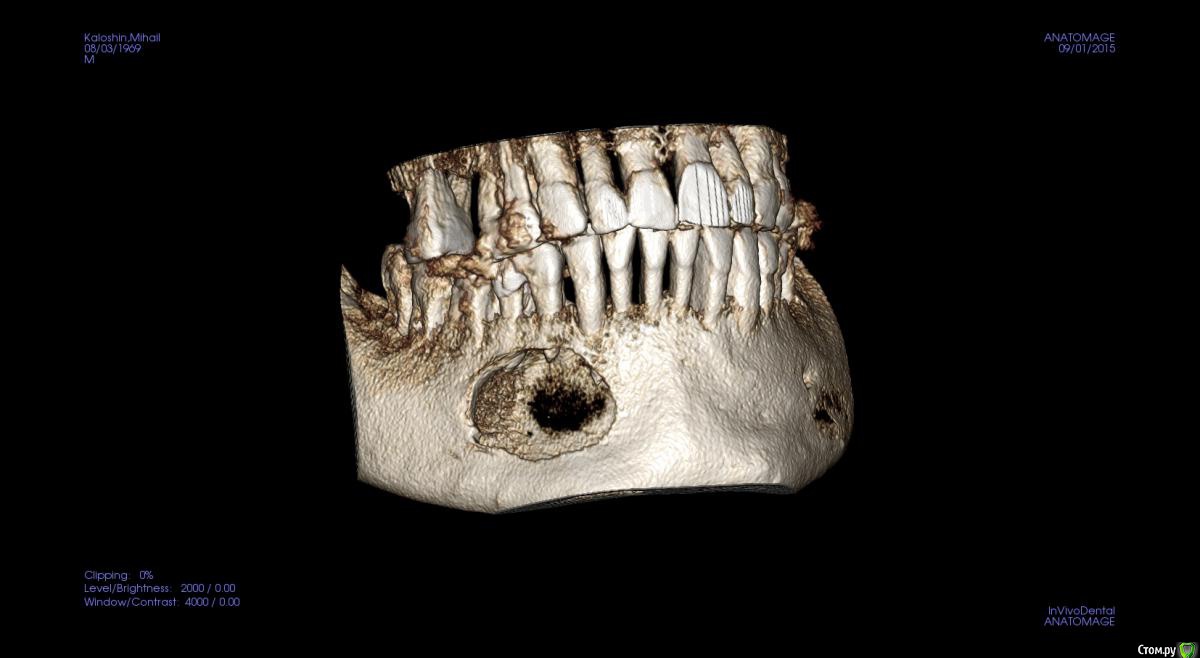

kamranchick Опубликовано 1 сентября, 2015 Поделиться Опубликовано 1 сентября, 2015 Не подскажите что с пациентом? пришел ставить мосты снизу и сверху, отправили на ОРТО, а тут такое... Ссылка на комментарий

kamranchick Опубликовано 2 сентября, 2015 Автор Поделиться Опубликовано 2 сентября, 2015 Артефакт наверное)сначала прицельный сделали, потом панорамный, потом на кт, везде одна и та же картина была Ссылка на комментарий

JDS Опубликовано 2 сентября, 2015 Поделиться Опубликовано 2 сентября, 2015 А может обширная генерализованная радикулярная киста?? Слева будто резидуальная. Не буду тыкать в небо, дождемся ответа опытных))) Ссылка на комментарий

pigmaleon Опубликовано 2 сентября, 2015 Поделиться Опубликовано 2 сентября, 2015 Радикулярная и резидуальная кисты. 1 Ссылка на комментарий

major Опубликовано 2 сентября, 2015 Поделиться Опубликовано 2 сентября, 2015 В ЧЛХ. Там ребята если не будут подстраховываться(биопсия и т.д.) прооперируют с формированием дефекта или без. Скорее всего остеосинтез пластинами планироваться будет возможно + костные блоки из гребня подвздошной. Возможен дистракционный остеогенез, если будет дефект. Заинтересованные зубы удаляются.Онконастороженность никто не отменял))) Материал на гистологию конечно же. Ссылка на комментарий